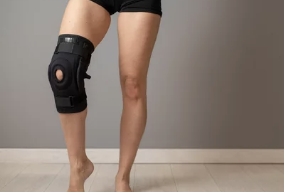

✅ 인공관절 치환술 (말기 관절염의 경우)

- 무릎 관절이 심하게 손상된 경우 인공관절로 대체

- 주로 60대 이상 고령 환자에게 시행

- 관절 내시경 수술은 회복 기간이 짧고 효과적이지만, 심한 경우 인공관절 수술이 필요할 수도 있음.